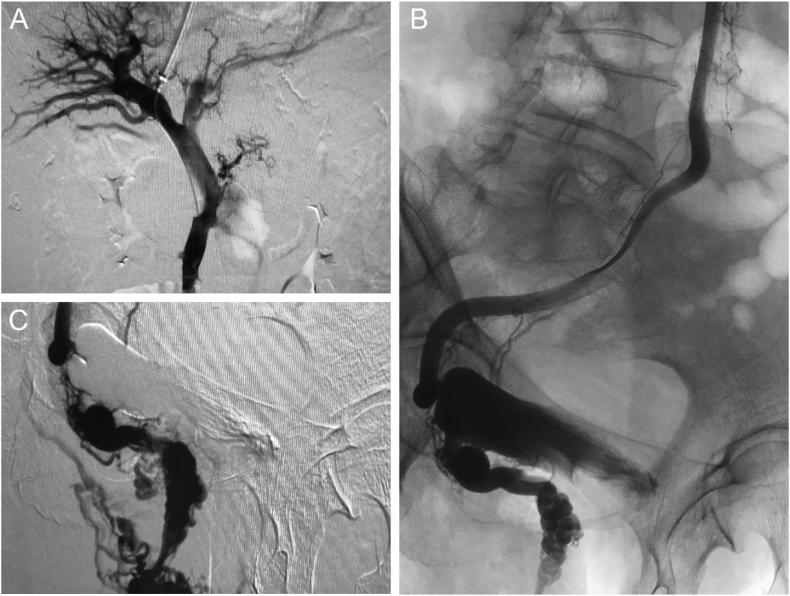

We report the case of a female patient with a 20-year history of hepatitis B virus infection who presented with repeated bleeding of hemorrhoids caused by severe portal hypertension with ectopic varices that is connection between the superior mesenteric vein and rectal venous plexus. Laboratory results revealed a hemoglobin level of 74 g/L. Finally, the patient was successfully treated with transjugular intrahepatic portosystemic shunt (TIPSS) placement without variceal embolization after a multidisciplinary comprehensive opinion. In the two-month follow-up period, the patient had failed to develop hepatic encephalopathy or hematochezia, and computed tomography venography (CTV) indicated that the stent was unobstructed and ascites disappeared.

TIPSS placement is effective for the case, and we hope this case can help improve clinicians' awareness of hemorrhoidal bleeding with severe portal hypertension. Portal hypertension should also be considered during the diagnosis and treatment, as opposed to hemorrhoidal bleeding alone. Moreover, abdominal CTV is recommended as an effective imaging examination method to determine the stent status after operation.

我们报告了一例有20年乙型肝炎病毒感染史的女性患者,该患者因严重门静脉高压伴异位静脉曲张(即肠系膜上静脉与直肠静脉丛之间的连接)导致反复痔疮出血。实验室检查结果显示血红蛋白水平为74 g/L。最后,经多学科综合评估后,患者成功接受了经颈静脉肝内门体分流术(TIPSS)植入,未进行曲张静脉栓塞。在两个月的随访期内,患者未发生肝性脑病或便血,计算机断层扫描静脉造影(CTV)显示支架通畅,腹水消失。

TIPSS植入对该病例有效,我们希望该病例能提高临床医生对严重门静脉高压症所致痔疮出血的认识。在诊断和治疗过程中,除了单独考虑痔疮出血外,还应考虑门静脉高压症。此外,建议采用腹部CTV作为确定术后支架状态的有效影像学检查方法。